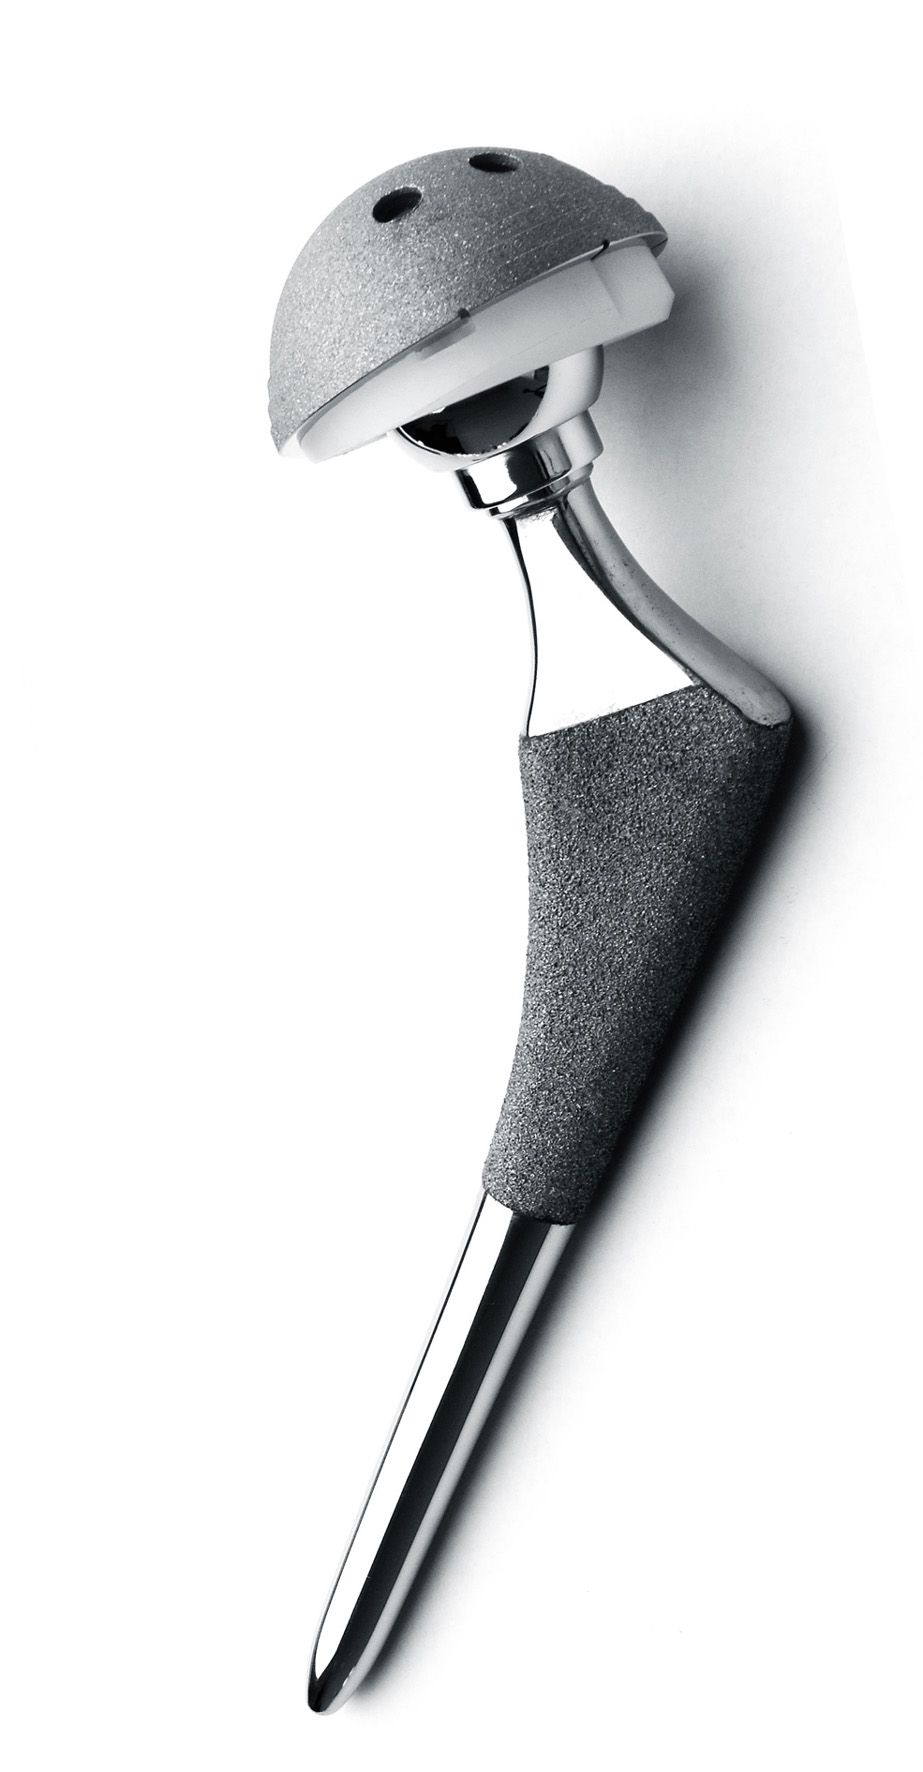

股骨頭人工假體

人工股骨柄假體

人工全髖關(guān)節(jié)假體